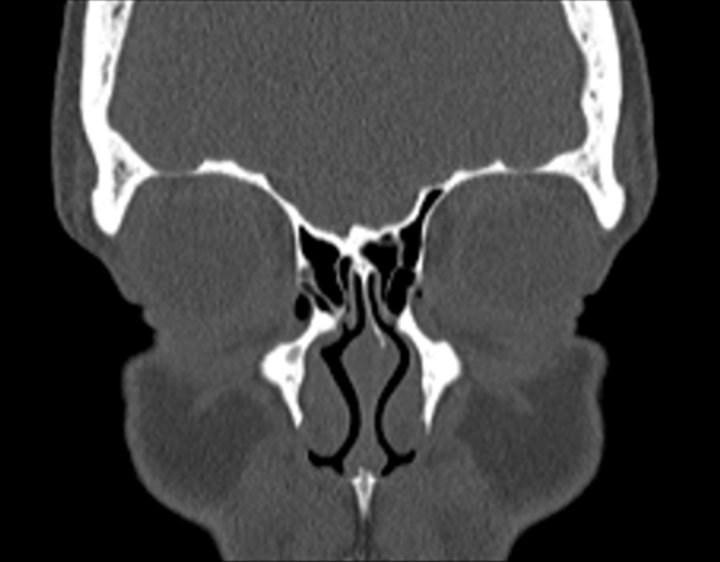

Click any image for labels.